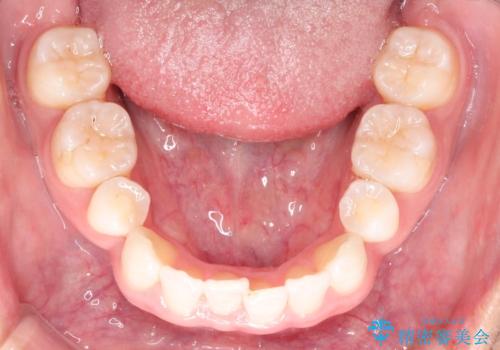

【インビザライン】笑った時の歯並びを綺麗にしたい

- 20代男性

- インビザライン

- 1年

- 笑った時の歯の見え方を綺麗にしたいことを主訴に来院されました。

インビザラインにて治療を行なっております。